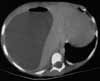

An ultrasonogram of the abdomen discloses a large hypodensity in the right lobe of the liver. The abdominal CT scan is shown here.

In view of the clinical picture and the abnormalities evident on the imaging studies, what is the most likely diagnosis?A. Amebic liver abscess